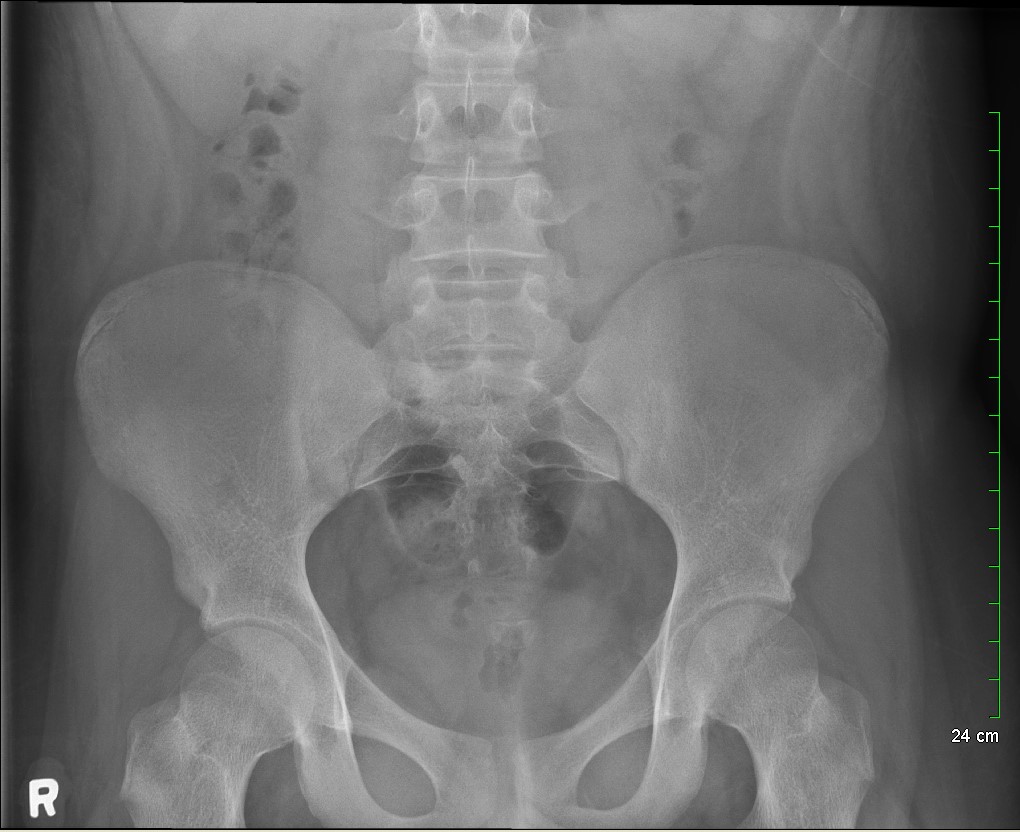

Because the patient presented with prolonged vomiting, a complete blood count (CBC), comprehensive metabolic panel (CMP), lipase, and kidney, ureter and bladder (KUB) was obtained. Initial labs showed only mild transaminitis and metabolic acidosis (AST 106, ALT 188, HCO3 15). KUB revealed the following images: